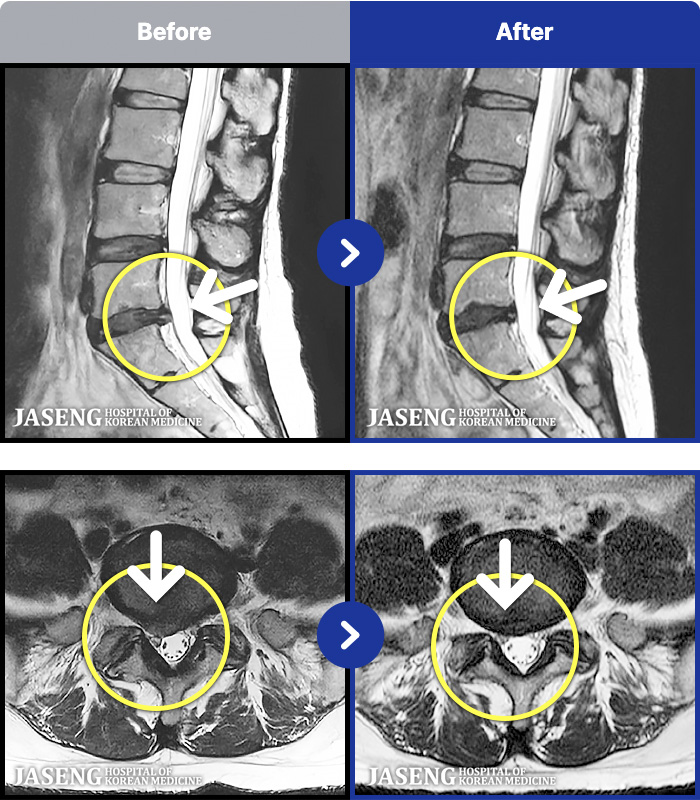

MRI ġ

1,301 MRI ũ ʸ Ȯϼ.